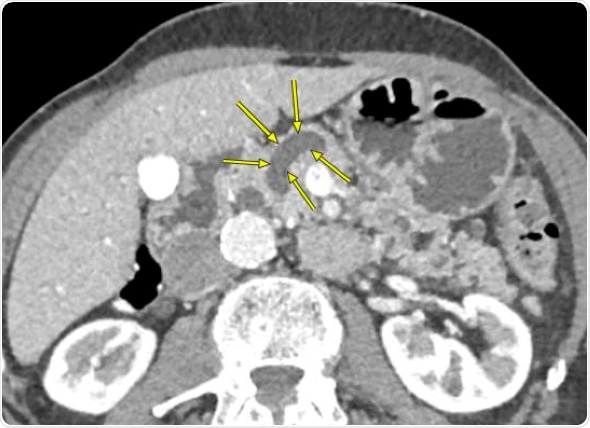

CT scan of a pancreas that shows enlarged pancreatic duct. Credit: Johns Hopkins Medicine

The pancreas is shaped vaguely like a revolver, with a duct --normally about 3 millimeters in diameter -- that runs all the way down the barrel of the gun and carries digestive enzymes. When inflamed or populated by cysts or other growths, the duct enlarges.

The vast majority of pancreatic cysts, including intraductal papillary mucinous neoplasms, are benign and cause no symptoms, the researchers note. In fact, most are diagnosed “incidentally” during MRIs or CT scans for non-pancreas-related conditions. But some can cause significant inflammation and damage to the duct that runs the length of the pancreas — a process that dilates, or enlarges, the duct — and are more likely precancerous or even cancerous.